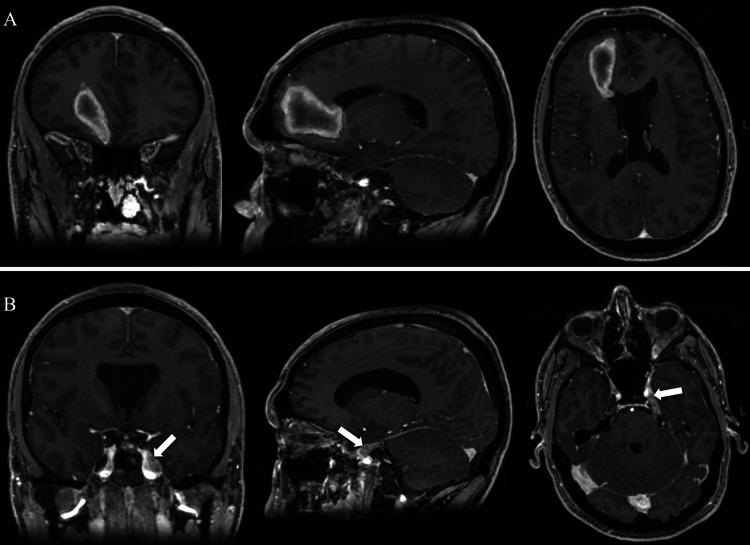

A case is presented of a 34-year-old man who presented with left facial numbness, multiple intracranial lesions, a lumbar intradural lesion, and diffuse spinal leptomeningeal involvement. A lumbar laminectomy and biopsy were performed, which revealed the diagnosis of extraskeletal Ewing sarcoma/primitive neuroectodermal tumor. The patient had a rapidly progressive clinical decline despite total neuroaxis radiation and multiple lines of chemotherapeutic treatments, eventually dying from his disease and its sequelae 6 months after diagnosis.

报告了一例34岁男性病例,该患者表现为左侧面部麻木、多发颅内病变、腰椎硬膜内病变以及弥漫性脊髓软膜受累。进行了腰椎椎板切除术和活检,结果显示为骨外尤因肉瘤/原始神经外胚层肿瘤。尽管进行了全神经轴放疗和多线化疗,患者的临床病情仍迅速进展,最终在诊断后6个月死于疾病及其后遗症。